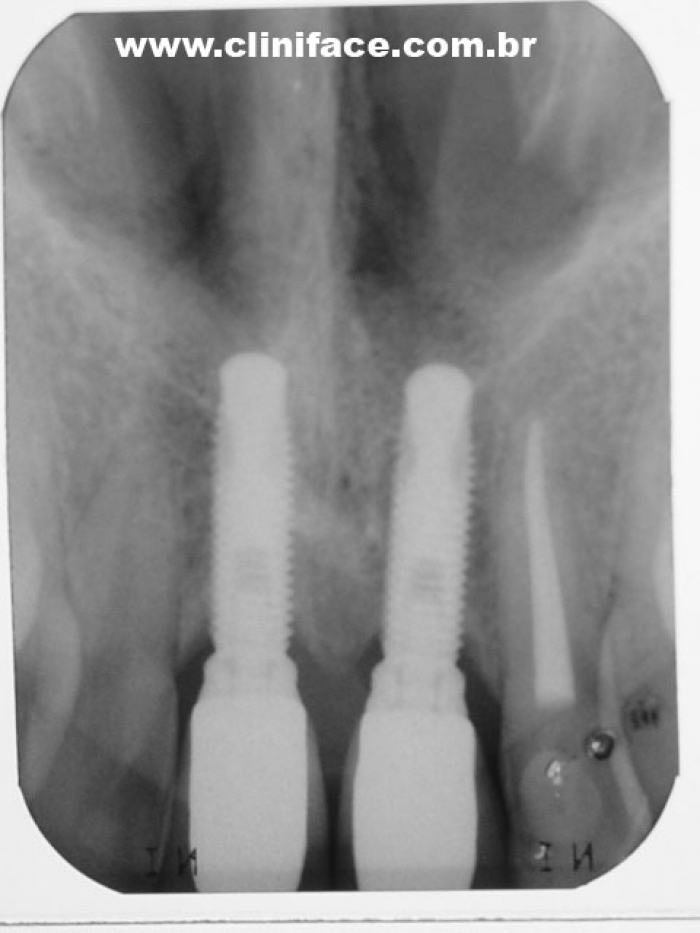

Raio X das próteses fixas em porcelana instaladas